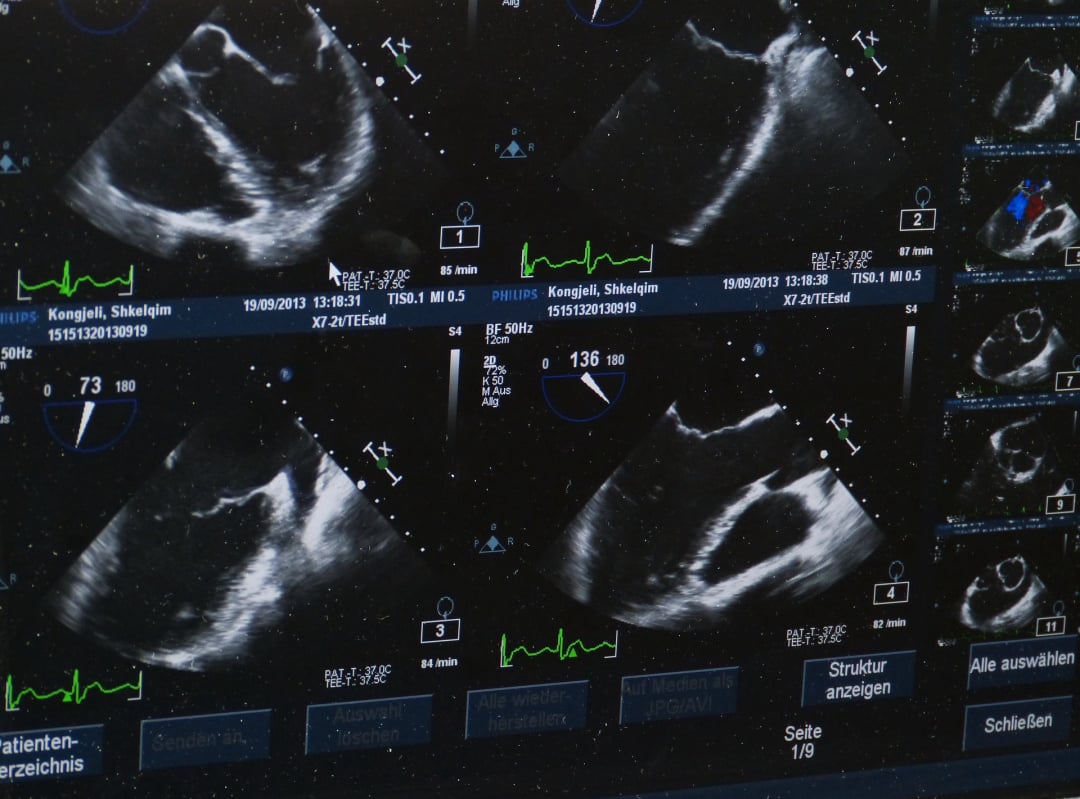

- Echokardiográfia szívizomzat és szelepek részletes vizsgálatára.